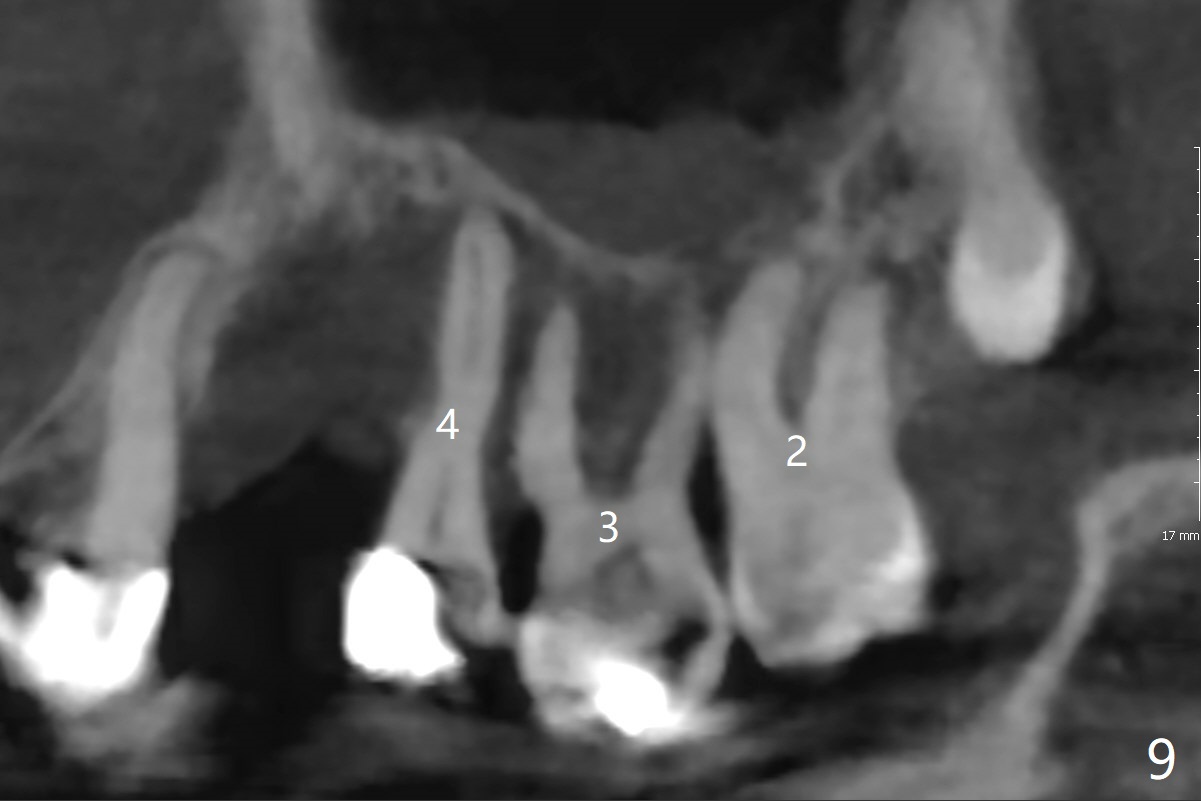

A 51-year-old woman has poor dentition with chronic periodontitis (Fig.1). She has financial constraint, but refuses RPD, insisting upon UR posterior implants first. After discussion of severe bone loss, she agrees with bone graft first (Fig.2-4). Since the bone atrophy is the most severe at #3 (Fig.5 coronal section; L: lingual), sinus lift (Fig.6 arrow) is conducted after extraction (black). Use sticky bone (Fig.7 red circles) and Titanium-reinforced Cytoplast (white) for socket preservation. Or if Magicore is able to achieve primary stability (Fig.8 green), an abutment (pink) will be placed for an immediate provisional (white). The latter are capable of holding bone graft in place. Since bone loss at #2 and 4 is less severe (Fig.9 sagittal section), their roots will act as walls to keep bone graft (Fig.11) in place after #3 extraction (Fig.10).